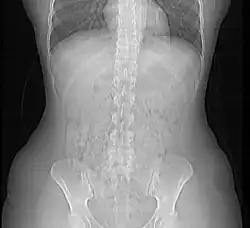

DCM-Beispielbild (siehe Text)

Das Bild rechts basiert auf einer DICOM-Datei. Zur Anzeige wurde es in ein Standard-Grafikformat konvertiert.